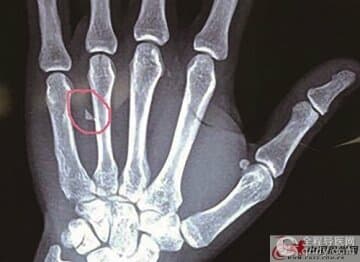

患者送至市一院后,院领导高度重视,立即组织相关科室专家联合会诊。经双源螺旋CT检查,三维图像显示:患者左侧盆、腹、胸贯通伤,棒状金属异物置入体内,左侧骶骨嵴前缘骨折,腹腔内积血,左侧气胸,左侧胸腔积血,左侧胸腔皮下积气,左侧10肋骨折,伤情危机生命!遂立即以胸腹部贯通伤急送至手术室急诊手术。